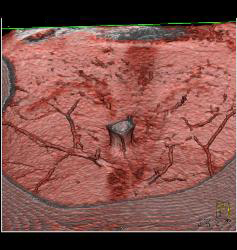

DIEP Flap Planning in 3D